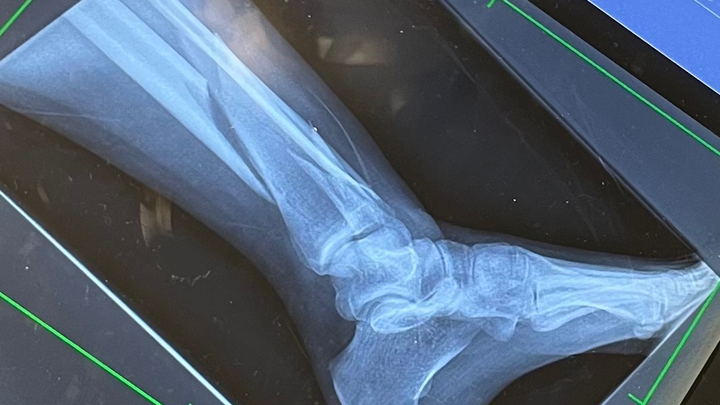

I was rushed to the ER. My partner en route, surrounded by strangers and in pain, I was out of my depth. After an X-ray and some morphine, I was told three things: that both bones in my left leg were broken, that my pain made sense, and that I would need to have surgery.

They sedated me, repositioned my floating bones, and put them in a temporary cast till my surgery. It hurt to move.